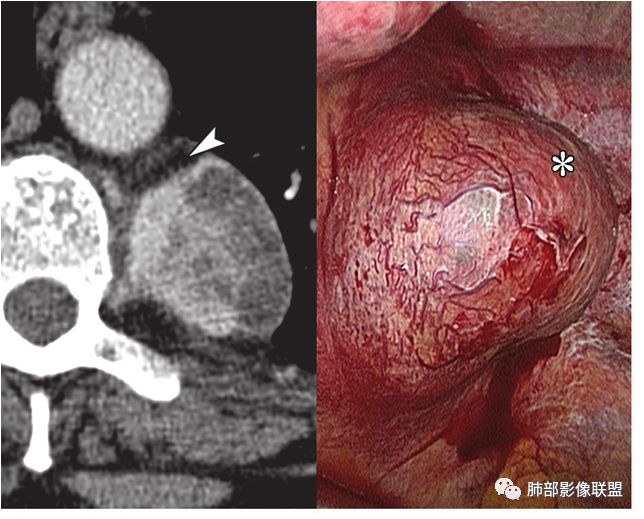

女,35岁 因“体检发现纵隔占位”入院,患者3天前体检发现肺部异常,外院胸部CT示右后纵隔占位,纵隔淋巴结影,未诉明显不适,无心慌胸闷,无头晕头痛,无恶心呕吐,无腹胀腹痛,无吞咽困难。

结果:巨大淋巴结增生病(Castleman,s, disease,CD)

(1)可发生于淋巴结存在的任何部位,60%-70%发生于胸部纵隔

(2)根据组织学特点分为透明血管型和浆细胞型两个基本类型,组织学共同点为具有完整的淋巴结结构、淋巴滤泡增生及血管增生

(3)影像表现上,多发单发的圆形或类圆形软组织密度影;透明血管型在CT增强扫描时早期可显著均匀强化,与大血管强化程度相似,原因在于有较多的供养血管,及病灶的毛细血管异常增生和扩展所致;而浆细胞型强化没有前者明显

(4)文献图片(A:透明血管型)